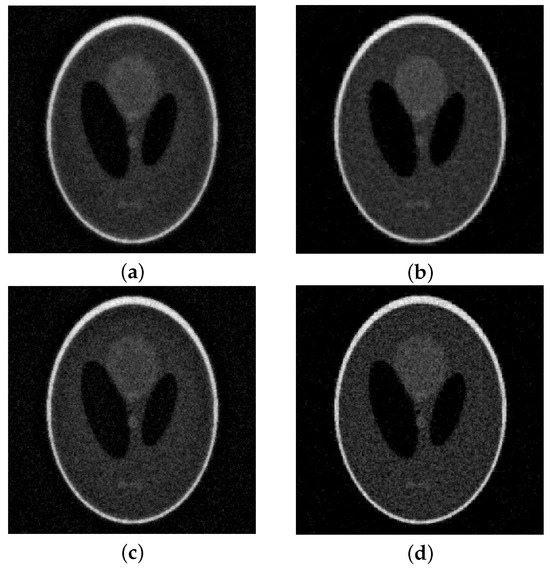

As above, we consider four levels of noise, namely and report the evolution of the RRE in Figure 6. We can observe that the obtained results are similar to the ones in the previous case, i.e., our method is more accurate and more stable, albeit requiring more iterations to converge. Moreover, as in the previous case, the highest stability is obtained for . This is confirmed by the results in Table 1. For the noise level , we report the solutions computed by lsqr and by the MGM with in Figure 7. Note that all the operators perform well, improving the stability of lsqr and keeping the same computational cost. However, has the lowest semi-convergence, especially with higher levels of noise and when the problem is strongly underdetermined due to the limited angles used.

Figure 7.

Shepp–Logan (limited angles) with 10% noise. On top of the reconstructions obtained at the DP iteration: (a) lsqr, (b) MGM, . At the bottom the optimal reconstructions: (c) lsqr, (d) MGM, .